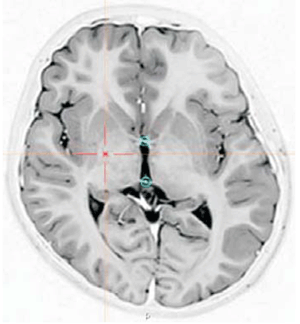

Se realizó implante de electrodos tetrapolares (Medtronic 3387) en globo pálido interno (GPi) posteroventral bilateral por vía estereotáctica bajo anestesia general. La planificación de los blancos cerebrales se llevó a cabo con el software de navegación estereotáctica Win Neus® 4.0 (Nuclemed, Argentina) mediante la fusión de imágenes de tomografía computada intraoperatoria con resonancia magnética preoperatoria (Figura 1).

Figura 1: Corte axial de resonancia magnética 1.5 T en el plano intercomisural; secuencia short-tau inversion recovery (STIR). Se observa la planificación del blanco en el GPi posteroventral derecho (cruz) y las comisuras blancas anterior y posterior (círculos).